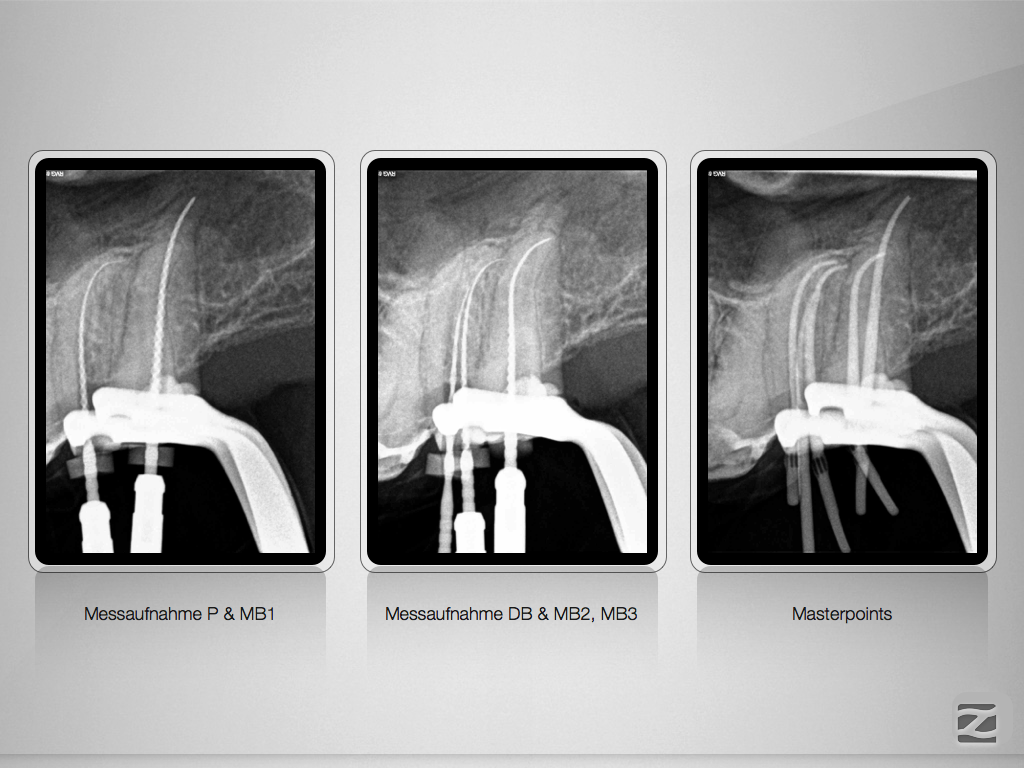

Hyflex Fallbeispiel (3/3)